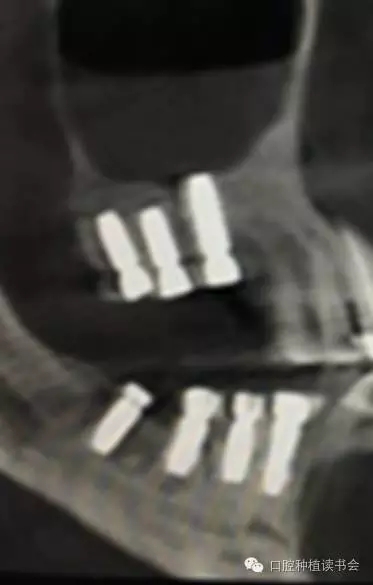

2、經(jīng)側(cè)壁開窗分離粘膜抬高竇底的方法稱為外提升(Lateral Window Technique)。早期由Philip?Boyne提出,后來上頜竇側(cè)壁開窗在粘膜和竇底之間進(jìn)行骨增量的術(shù)式逐步應(yīng)用開來。側(cè)壁開窗后是否同期植入種植體,根據(jù)RBH,種植體穩(wěn)定性的預(yù)判而決定??偟膩碚f,上頜竇外提升術(shù)的成功率86%~100%(Jensen,2009)。根據(jù)CBCT圖像,不但可以提供術(shù)前的種植計(jì)劃指導(dǎo),而且上頜竇外提升術(shù)后的效果,尤其是檢查種植體腭側(cè)是否有植骨不全,都會一目了然。(圖10-12)